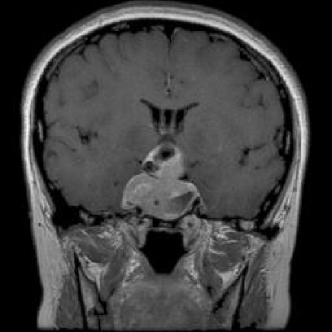

4.1.6 Brain MRI

Brain tumors pose significant health challenges, often impacting critical functions such as vision, balance, and cognition. Early detection is crucial for improving patient outcomes and quality of life. Through MRI scans, different conditions of the brain can be visually detected. The selected brain tumor dataset 666https://www.kaggle.com/datasets/sami009mr/brain-tumor-dataset contains 3,362 images across four categories: glioma, meningioma, pituitary tumors, and normal brains. Images illustrating the three aforementioned classes can be found in Fig. 7.

Refer to caption

(a) No tumor

(b) Glioma tumor

(c) Meningioma tumor

(d) Pituitary tumor

Figure 7: Brain MRI scans.